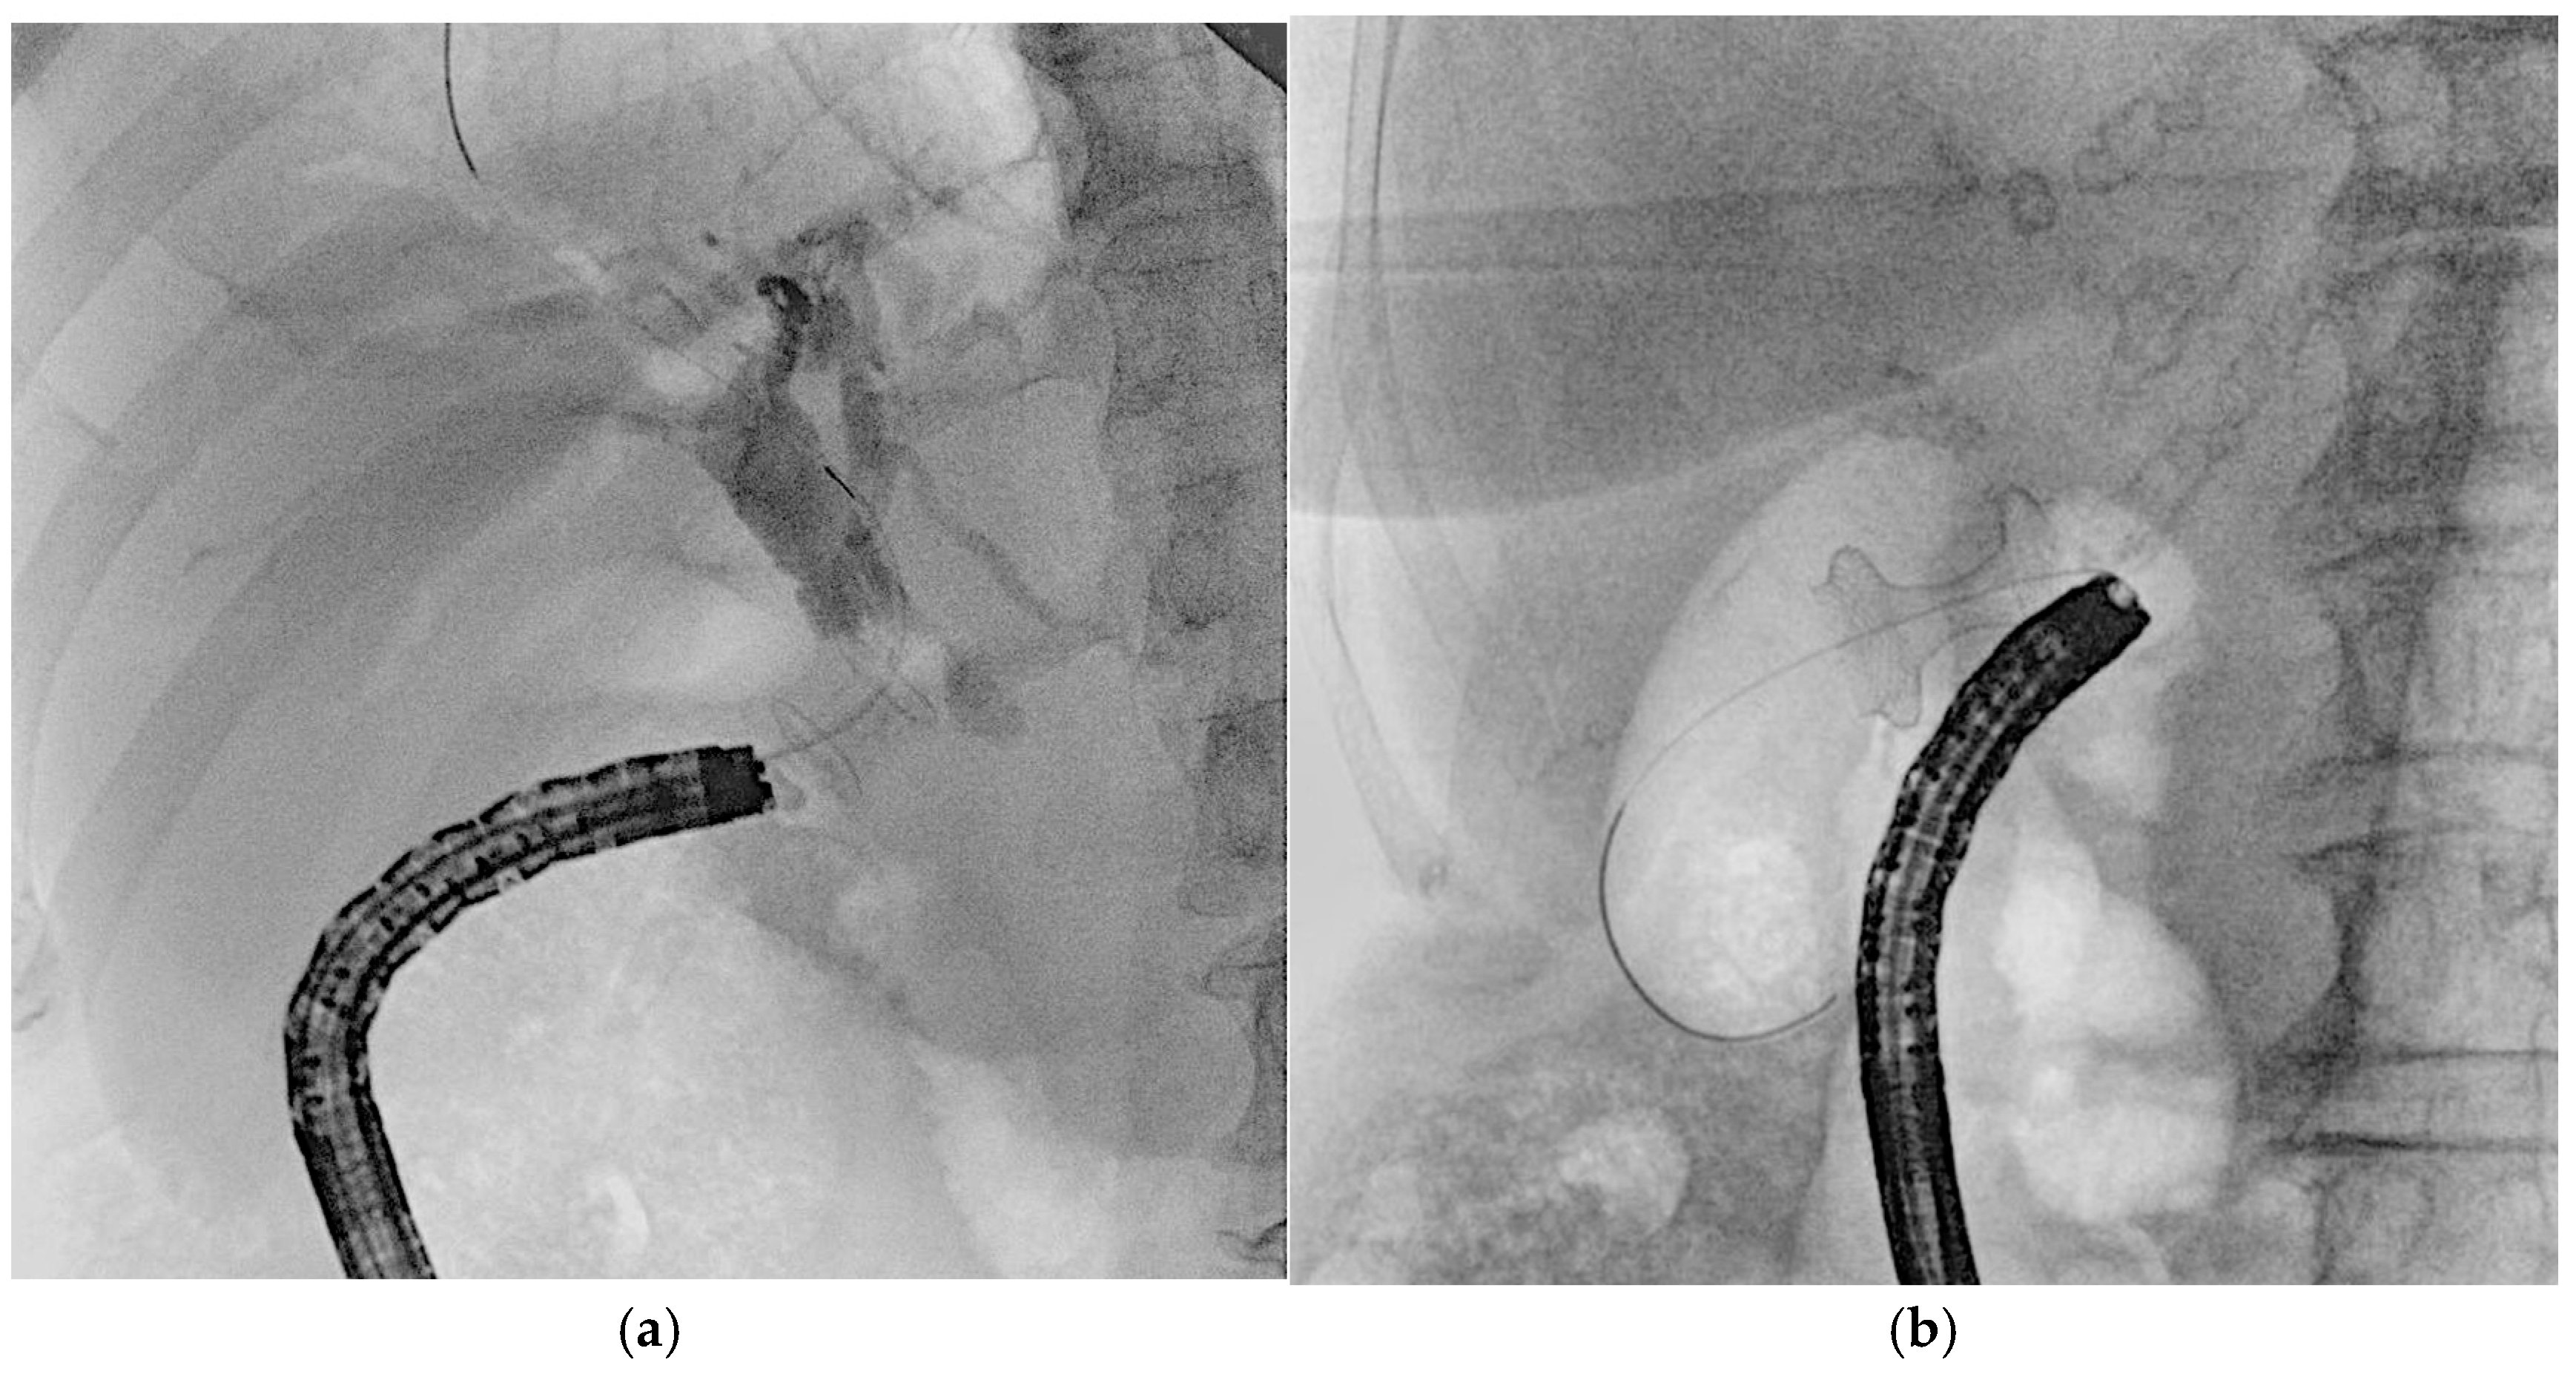

4.3. Other EUS-Guided Procedures

EUS-guided procedures have increasingly adopted lumen-apposing metal stents (LAMSs), revolutionizing various interventions by simplifying access and enhancing procedural efficiency. One of the most significant applications is in the drainage of pancreatic fluid collections or walled-off necrosis, where traditional transmural drainage relied on double-pigtail plastic stents and long guidewires to facilitate device exchanges [2]. The introduction of electrocautery-enhanced LAMSs has minimized the need for guidewires in freehand techniques; however, they remain essential after initial stent deployment. Guidewires can be preloaded into the stent catheter or inserted post-placement to aid further interventions, facilitate LAMS dilation, and enable the coaxial placement of plastic stents [2]. In cases where echoendoscope instability is a concern, placing a guidewire before LAMS deployment can improve stability, reduce technical complications, and serve as a rescue option, such as the “LAMS-in-LAMS” technique [58]. In EUS-guided gastroenterostomy (GEA), LAMSs allow for both direct puncture and guidewire-assisted techniques, though the latter may increase the risk of stent misdeployment [59], due to the potential for guidewire manipulation to displace the bowel [60]. Similarly, EUS-guided choledochoduodenostomy (EUS-CDS) and gallbladder drainage (EUS-GBD) have become effective alternatives for managing biliary obstructions and acute cholecystitis (Figure 9) [61]. LAMSs have significantly improved these procedures, enabling both freehand and over-the-guidewire techniques. Typically, a 19-gauge needle is used for puncture, with guidewires of 0.035-inch or 0.025-inch diameter facilitating stent placement. The 0.025-inch Jagwire Revolution (Boston Scientific, USA) has been noted for its enhanced stiffness, providing a balance between rigidity and maneuverability, which fits for this kind of procedures [34]. In EUS-GBD, the use of a thin 22-gauge EUS-FNA needle can reduce complications like bile leakage, while the 0.018-inch guidewire (e.g., Fielder 18, Asahi Intecc, Japan) has shown promise in improving procedural outcomes [62]. Overall, LAMSs have streamlined EUS-guided procedures, reducing the need for repeated guidewire exchanges while maintaining their role in ensuring technical success.

Figure 9. (a) Guidewire-assisted advancement of a double-pigtail stent through an 8 × 8 mm lumen-apposing metal stent (LAMS) used for choledochoduodenostomy (EUS-CDS) to secure biliary drainage and prevent LAMS obstruction; (b) EUS-guided gallbladder drainage (EUS-GBD) performed using an electrocautery-enhanced lumen-apposing metal stent (LAMS). A 0.035-inch guidewire was used to improve stability and maintain access during deployment.